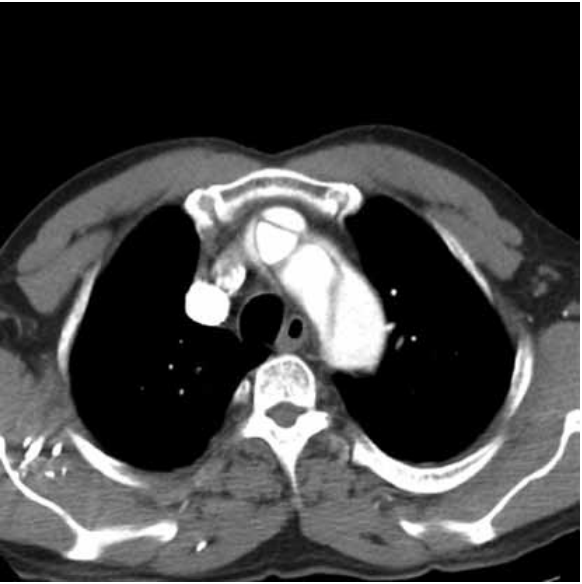

Paciente hipertenso em uso atual de 3 anti-hipertensivos inicia dor torácica de forte intensidade, em “facada”, com irradiação parar dorso. Frequência cardíaca de 90 bpm e pressão arterial de 220 x 120 mmHg. Eletrocardiograma mostra sobrecarga atrial e ventricular esquerdas. Realizou a angiotomografia a seguir.

O nível-alvo de pressão arterial sistólica a ser atingido idealmente em 20 minutos é